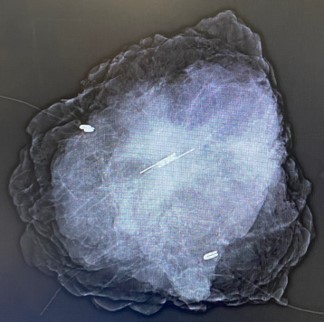

Which performed under general anesthesia with selective intubation intraoperative mammogram was done after the resection confirming the clip at the center of the specimen.

Figure 3: Intra operative mammogram for the left breast excision Specimen showing the SAVI reflector in the middle of the tissue.